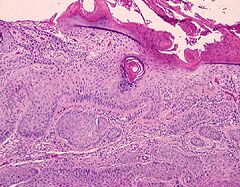

Low power. Invasion of the dermis by abnormal

epidermal cells. Note the presence of keratin (pink

areas) on the tumour surface and within the

epidermis.

In the histological slide, a squamous cell carcinoma has the following features:

• dermal invasion by abnormal cells from the epidermis

• pleomorphism of the tumour cells

• presence of keratinization within the cells which give the cells abundant pink cytoplasm,  (this may be absent in poorly differentiated type). Intraepithelial keratin in the shape of a whorl is termed squamous eddy or pearl.

• at high power intercellular bridges are commonly seen.